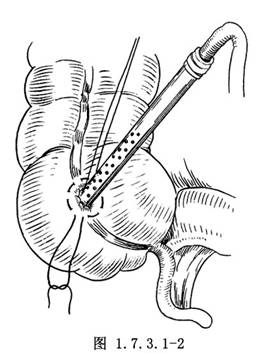

2.从切口插入双导管吸引管,吸出肠内容物(图1.7.3.1-2)。